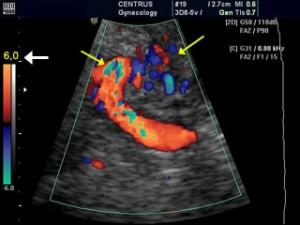

Doppler ultrasound monitors how speed of blood flow moving in the umbilical, enabling clinicians to determine if the fetus is healthy, abnormal, or under stress. This allows the physician to determine the proper course of treatment.